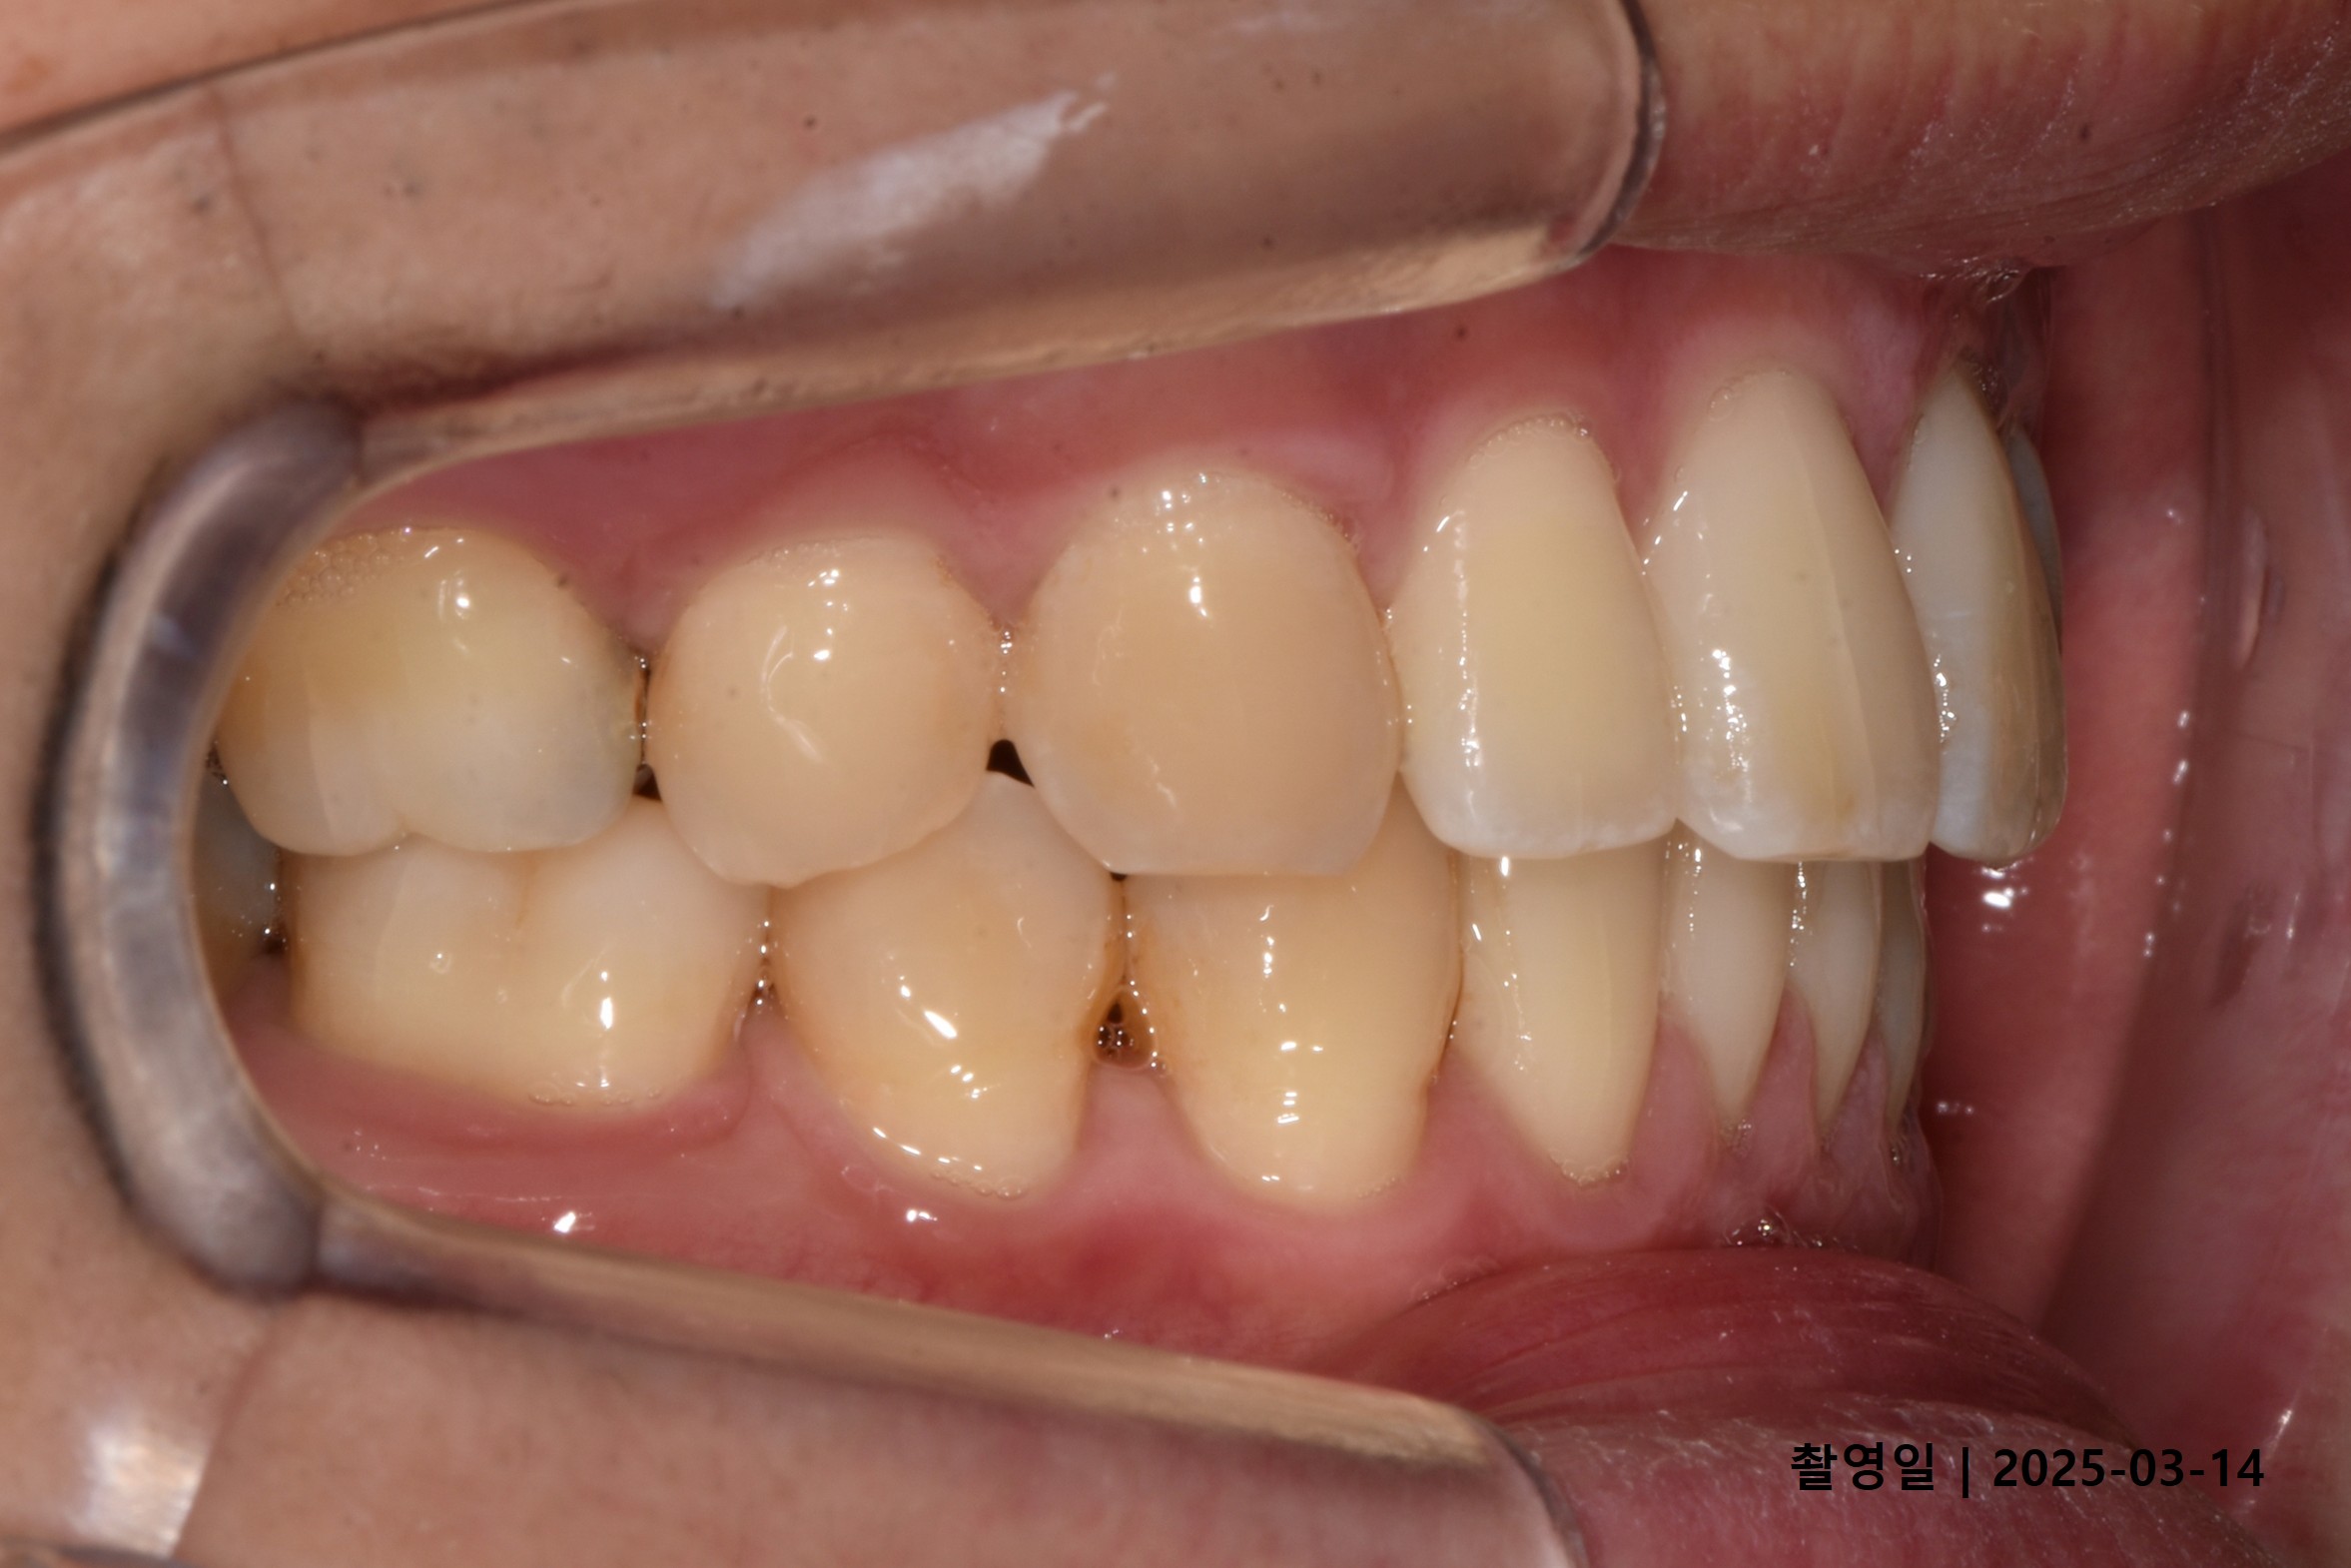

Case 2

- 24세 여성

- 상하악소구치 발치

- 치료기간 2년 1개월

치료 전

치료 후